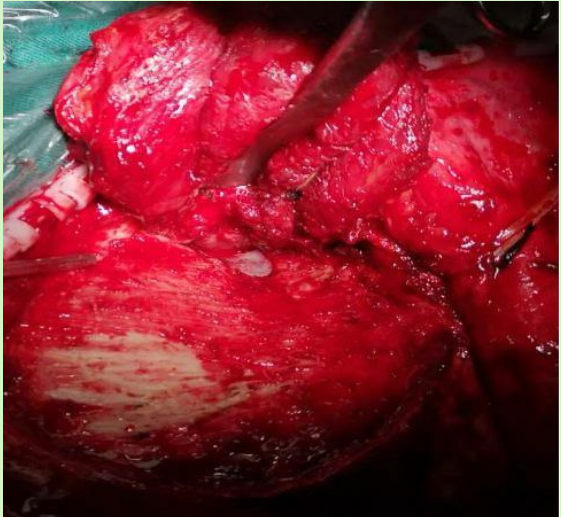

切开瘤膜,分块切除肿瘤

分离瘤膜边界,完整切除肿瘤

肿瘤残腔显示